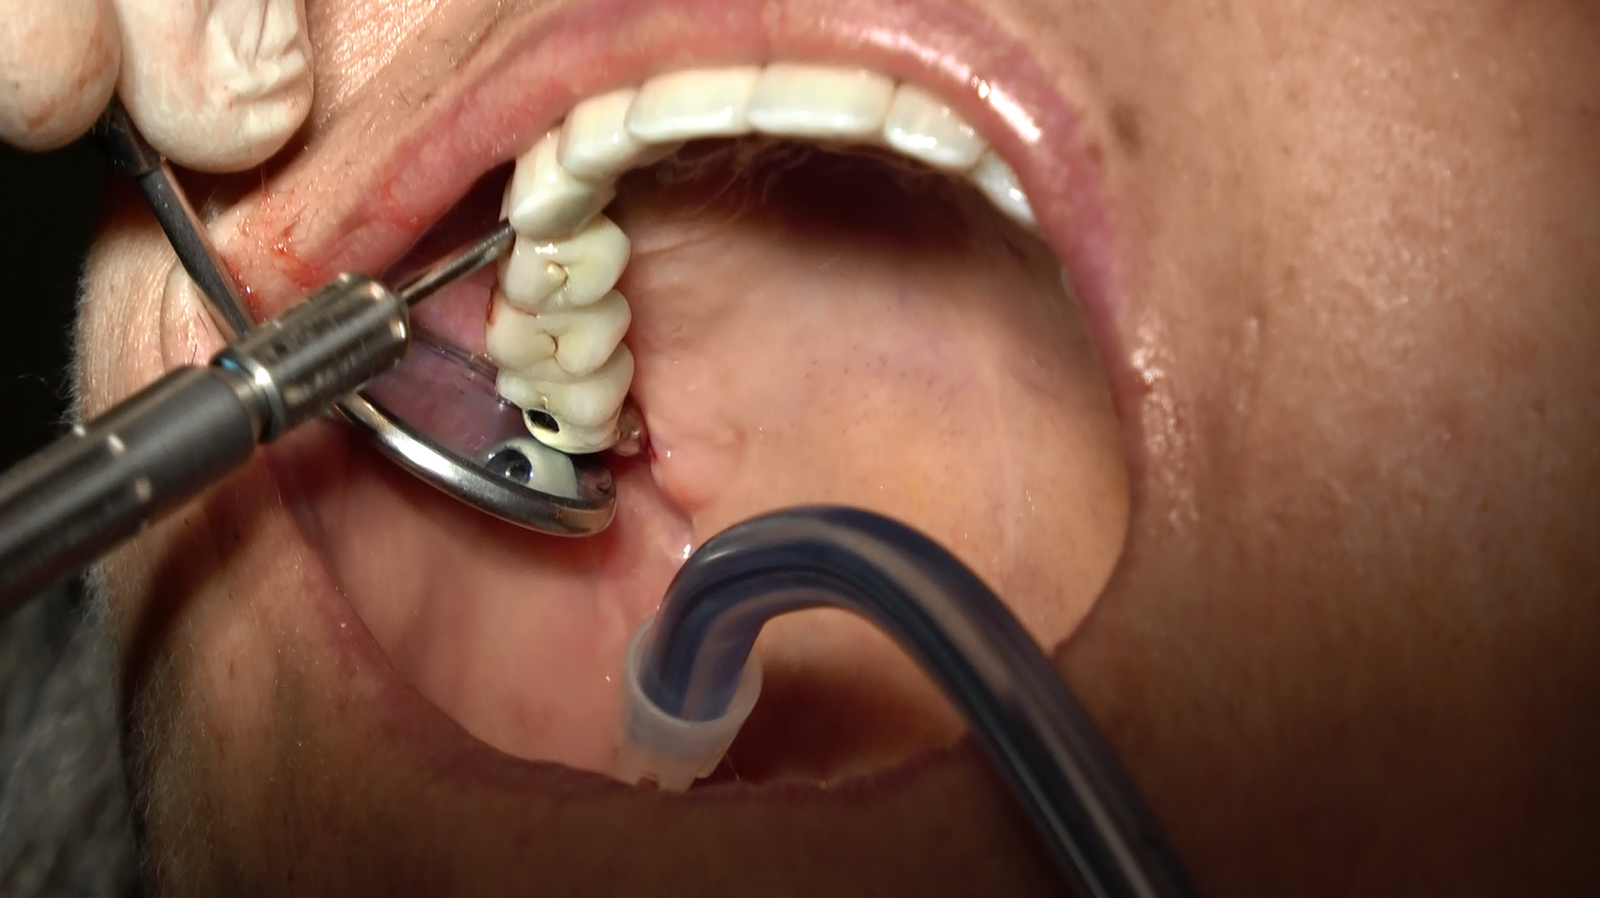

- Procedura Chirurgica Minimamente Invasiva: L’intervento è stato eseguito con un approccio minimamente invasivo, riducendo il trauma e accelerando il periodo di guarigione.

- Posizionamento degli Impianti Sottoperiostei: Gli impianti sono stati posizionati direttamente sulla superficie dell’osso mascellare, garantendo stabilità e supporto adeguati.